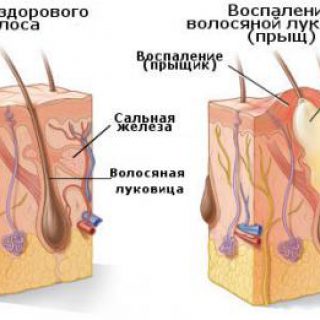

Прыщи на руках чешутся — почему, как лечить. Почему появляются прыщ на пальцах рук

Прыщи на руках чешутся — почему, как лечить. Почему появляются прыщ на пальцах рук

Прыщ в ухе, за ушами, прыщи на затылке: распространенные причины, виды и способы лечения

Прыщ в ухе, за ушами, прыщи на затылке: распространенные причины, виды и способы лечения